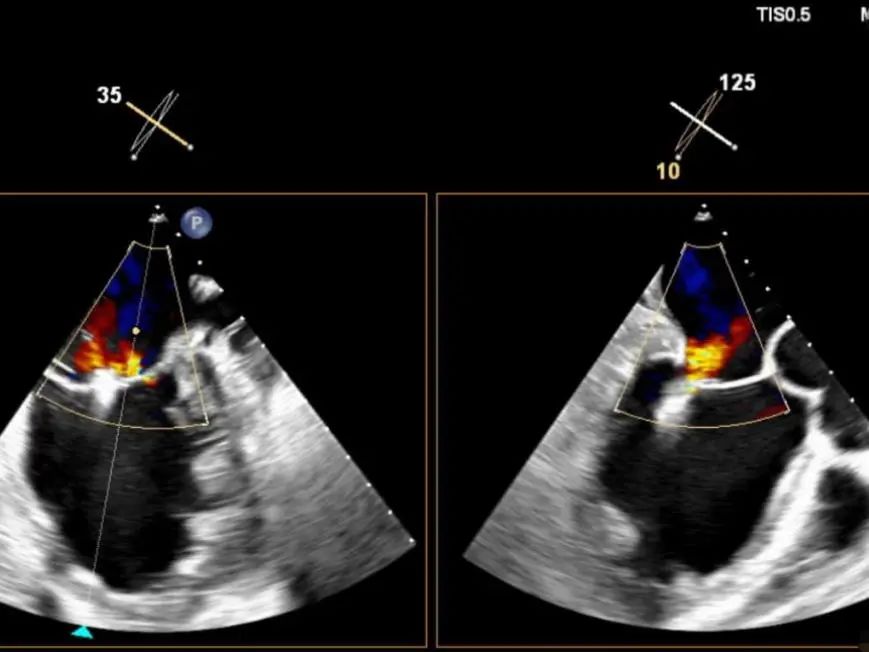

术前TEE(3+)

手术过程:手术采用经右侧股静脉入路,在TEE和DSA引导下完成房间隔穿刺,位置偏后偏上,穿刺高度为3.9厘米。置入瓣膜夹系统后,在左房调整瓣膜夹的轴向(orientation)和前进轨迹(trajectory),后进入左室进行瓣叶抓捕。由于两个瓣叶无法对合,后瓣叶较短,在尝试同时抓捕几次后,决定使用单独抓捕功能。先抓捕前瓣叶,再抓捕后瓣叶,确认瓣叶插入长度足够,缓慢关闭瓣膜夹。即刻返流程度降至轻度,跨瓣平均压差为2mmHg,最终成功释放瓣膜夹。采用“8”字缝合法关闭股静脉入路。术后肺静脉逆流和左房压都明显好转,预示着良好的预后。手术共耗时2小时,术后患者无明显不适,安返CCU继续观察。